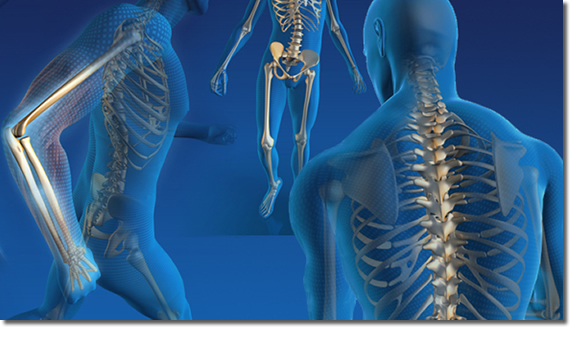

La Traumatología y Ortopedia, es una especialidad de la medicina, dedicada específicamente a las enfermedades del sistema musculo-esquelético.

• Deformidades de extremidades

- Genu valgo

- Genu varo

- Columna (escoliosis)

- Juanetes